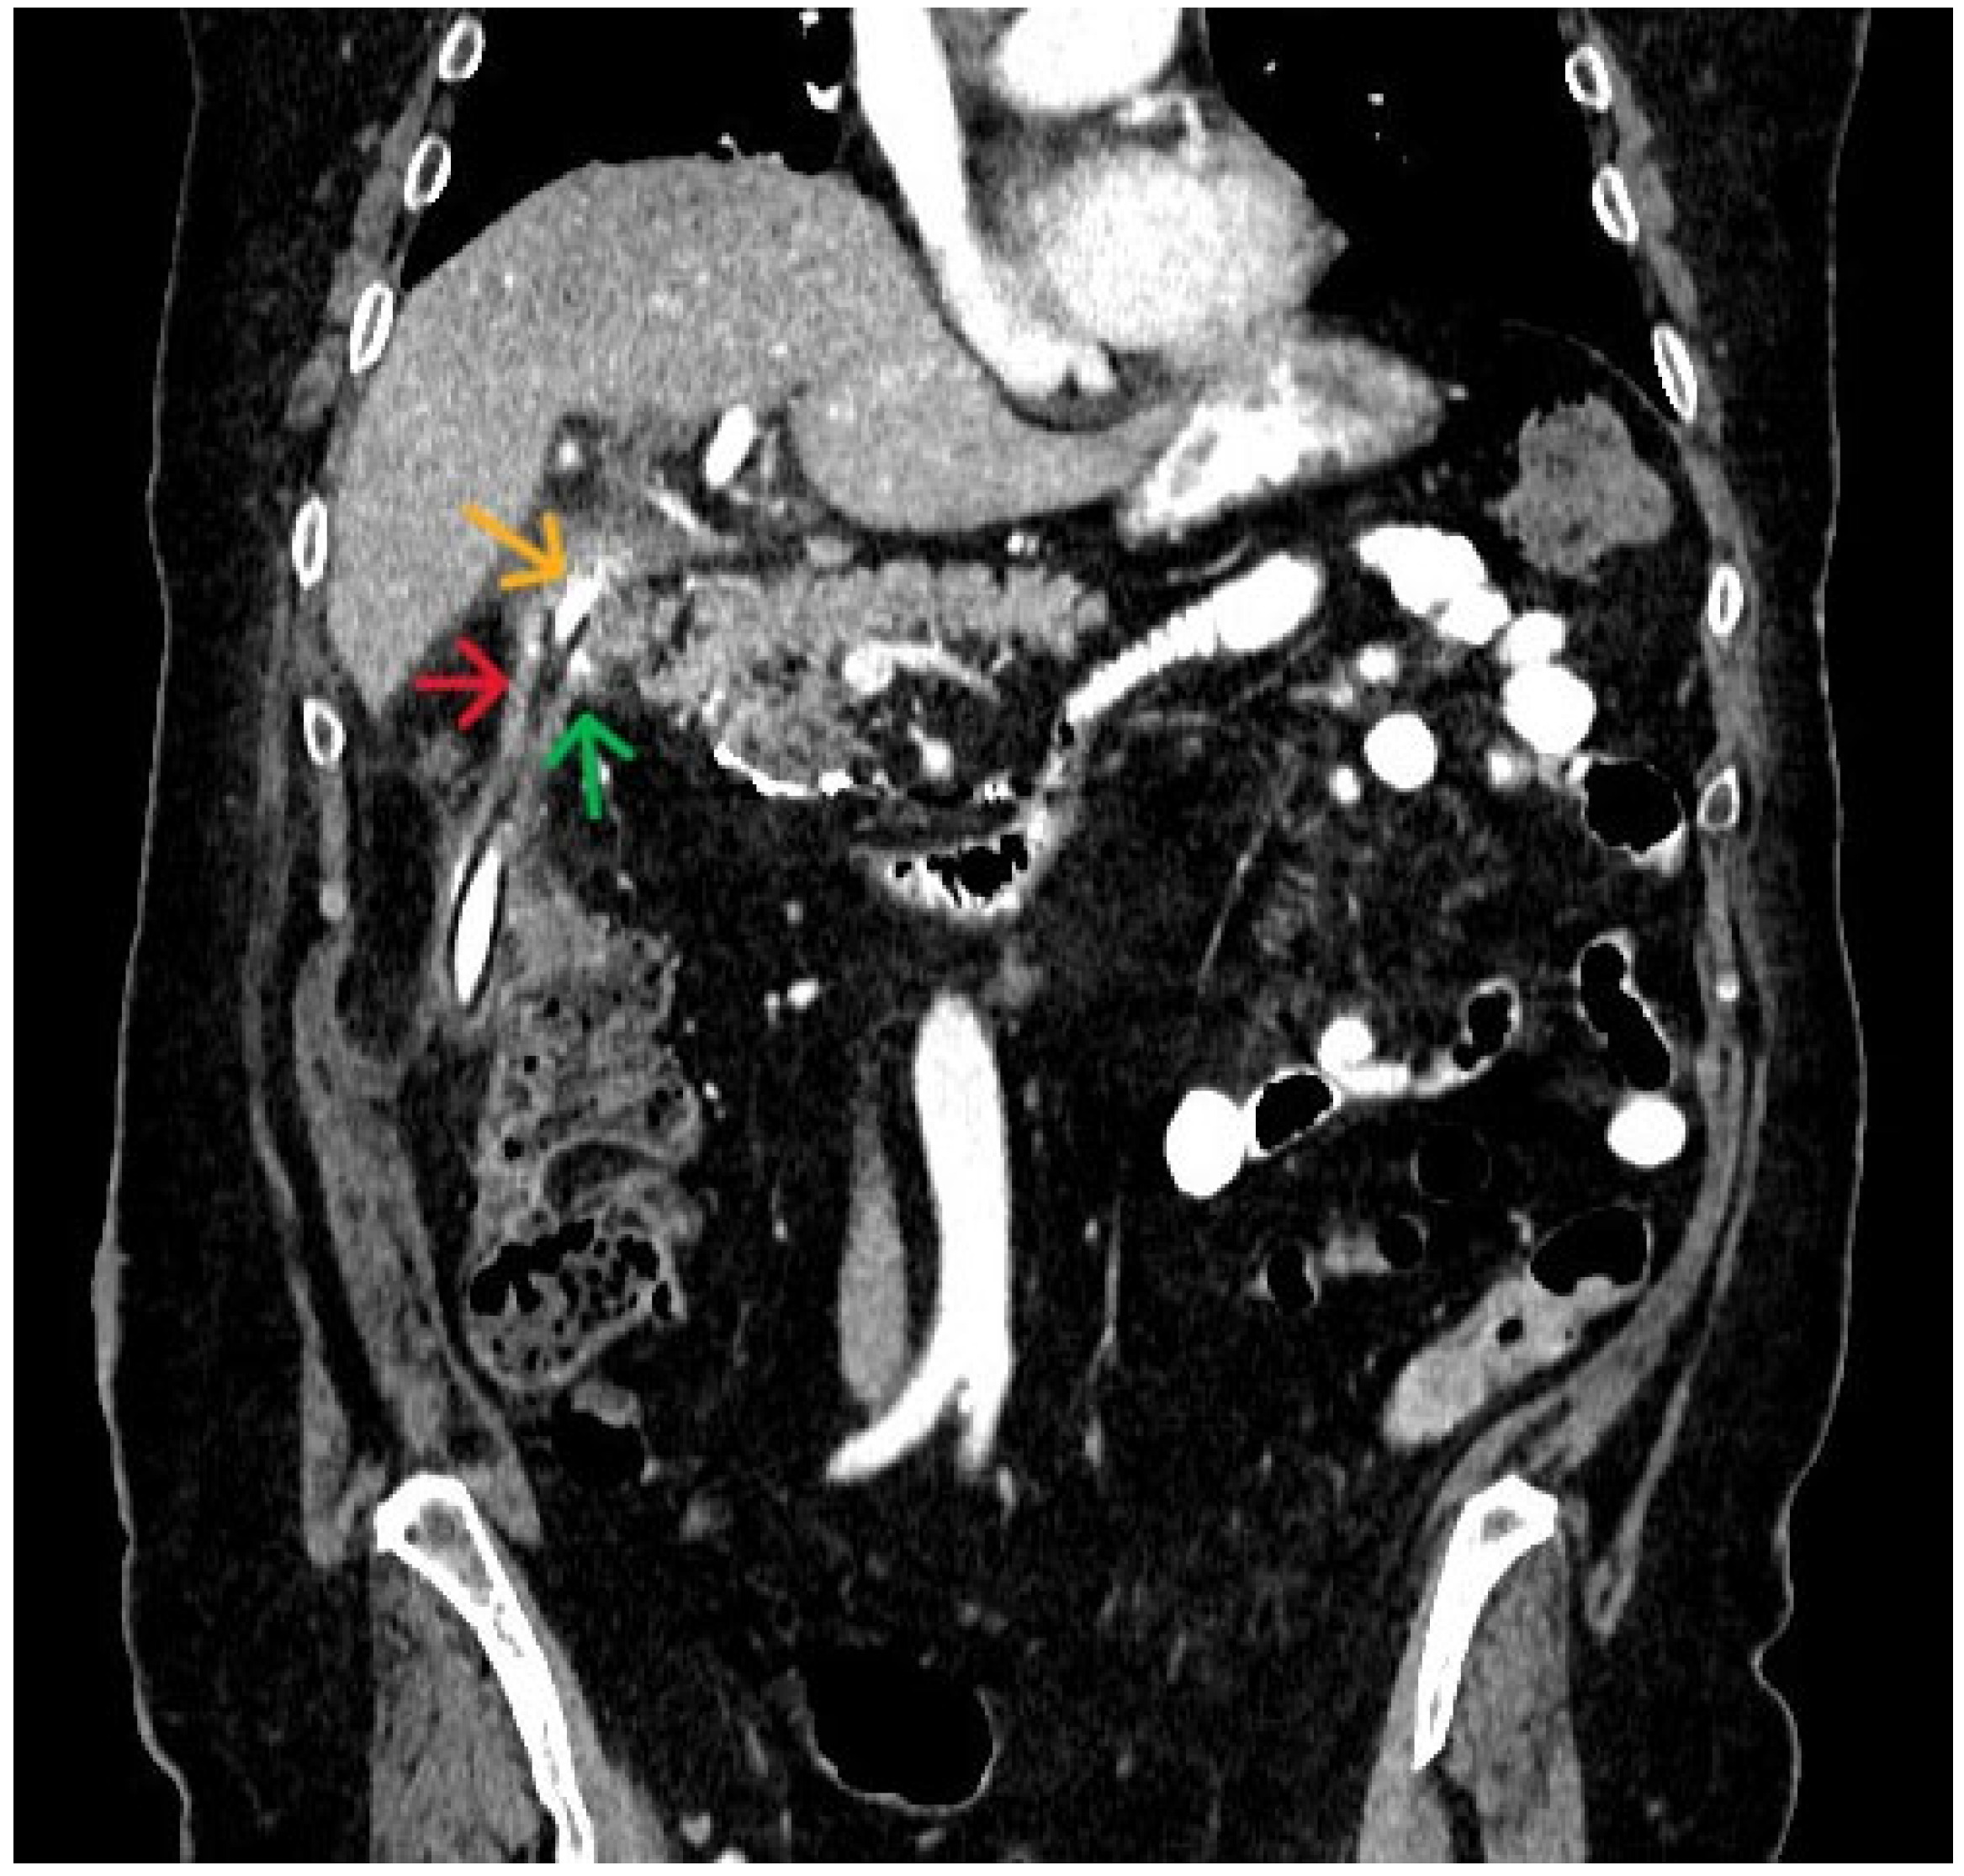

3. Case Presentation